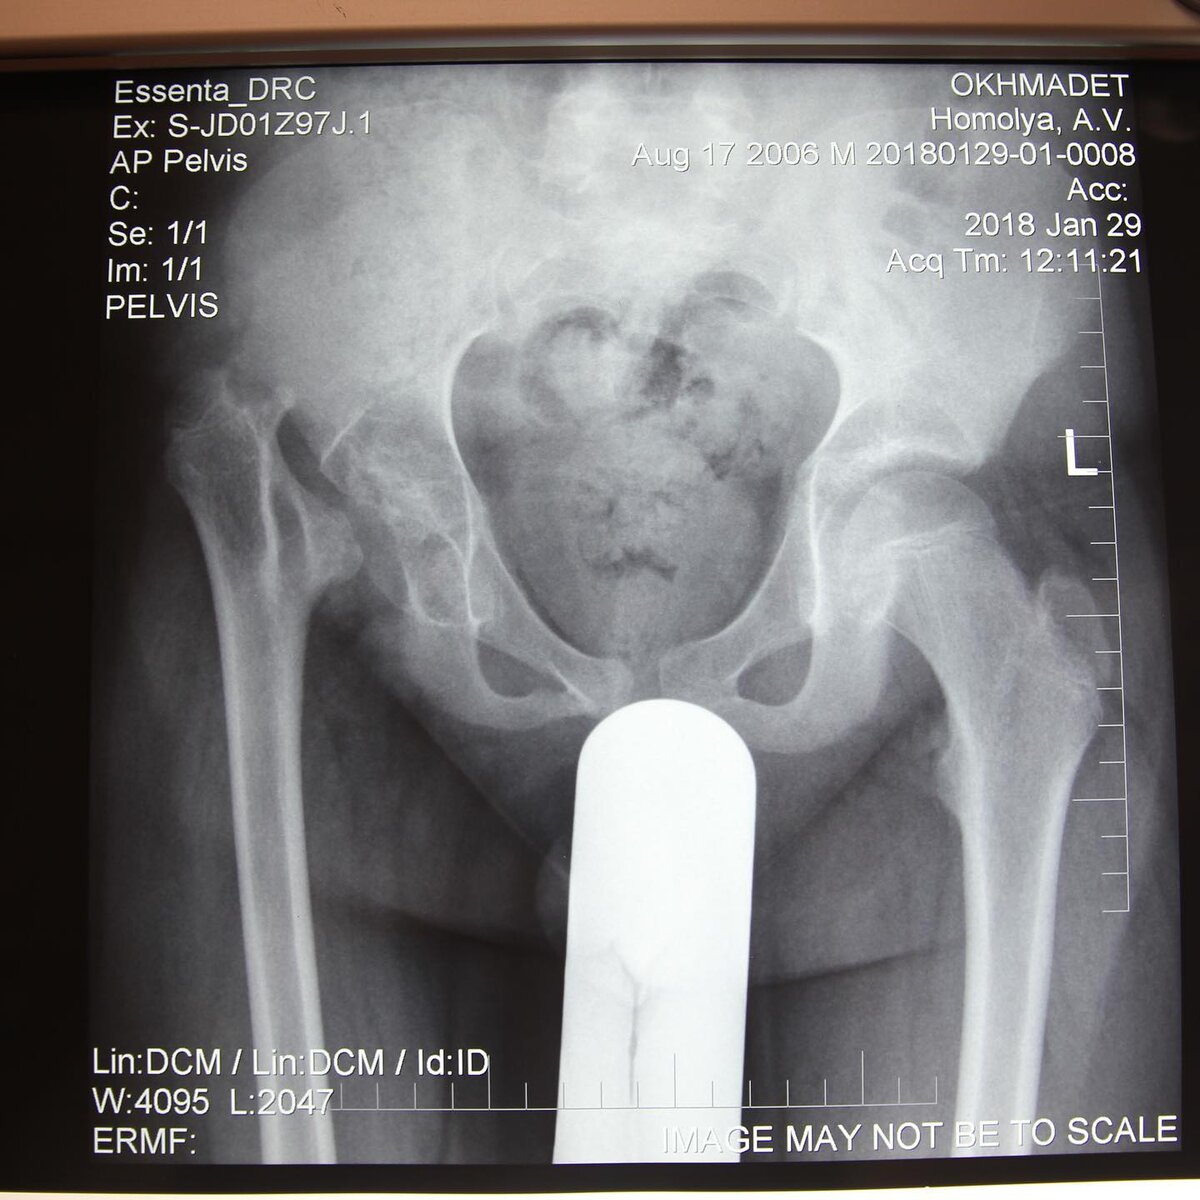

Сегодня я Вам расскажу об одном мальчике, ему было 12 лет, когда в 2018 году он попал к нам в клинику на лечение, со следующим диагнозом:

- Патологический вывих правого бедра после перенесённого гнойного коксита. Укорочение правого бедра и голени на 5 см.

Мы сделали одну операцию: операция Шанца-Илизарова с одновременным удлинением. Вот результат проделанной работы.

Рентген патологии

До лечения